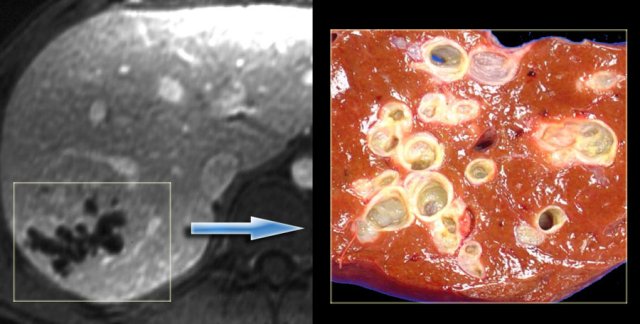

In some of the cases of Caroli disease the imaging findings may simulate a cystic neoplasm as is seen in the case on the left.

This case was originally diagnosed as a biliary cystadenoma.

However, the gross specimen demonstrates dilated bile ducts and ductal plate malformation was present microscopically.